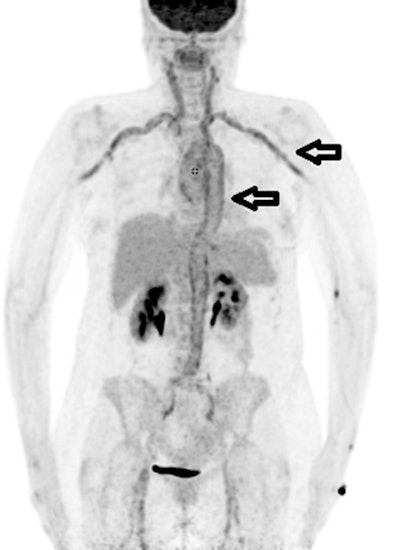

F-18 FDG PET/CT is effective for diagnosing fevers of unknown origin in more than half of cases after other imaging approaches have failed, according to a study published February 3 in Scientific Reports.

The study results revealed that PET/CT was the decisive examination for establishing the final diagnosis in 54% of patients. F-18 FDG-PET/CT findings were equivocal and indecisive in 13.3% and false positive in 3.3%. A normal F-18 FDG pattern was present in 29.3% of patients.

The largest part of final diagnoses was assorted to infectious diseases (109/300 patients, 36.3%) followed by autoimmune/rheumatic diseases (51/300 patients, 17%) and malignancy (33/300 patients, 11%), according to the findings.